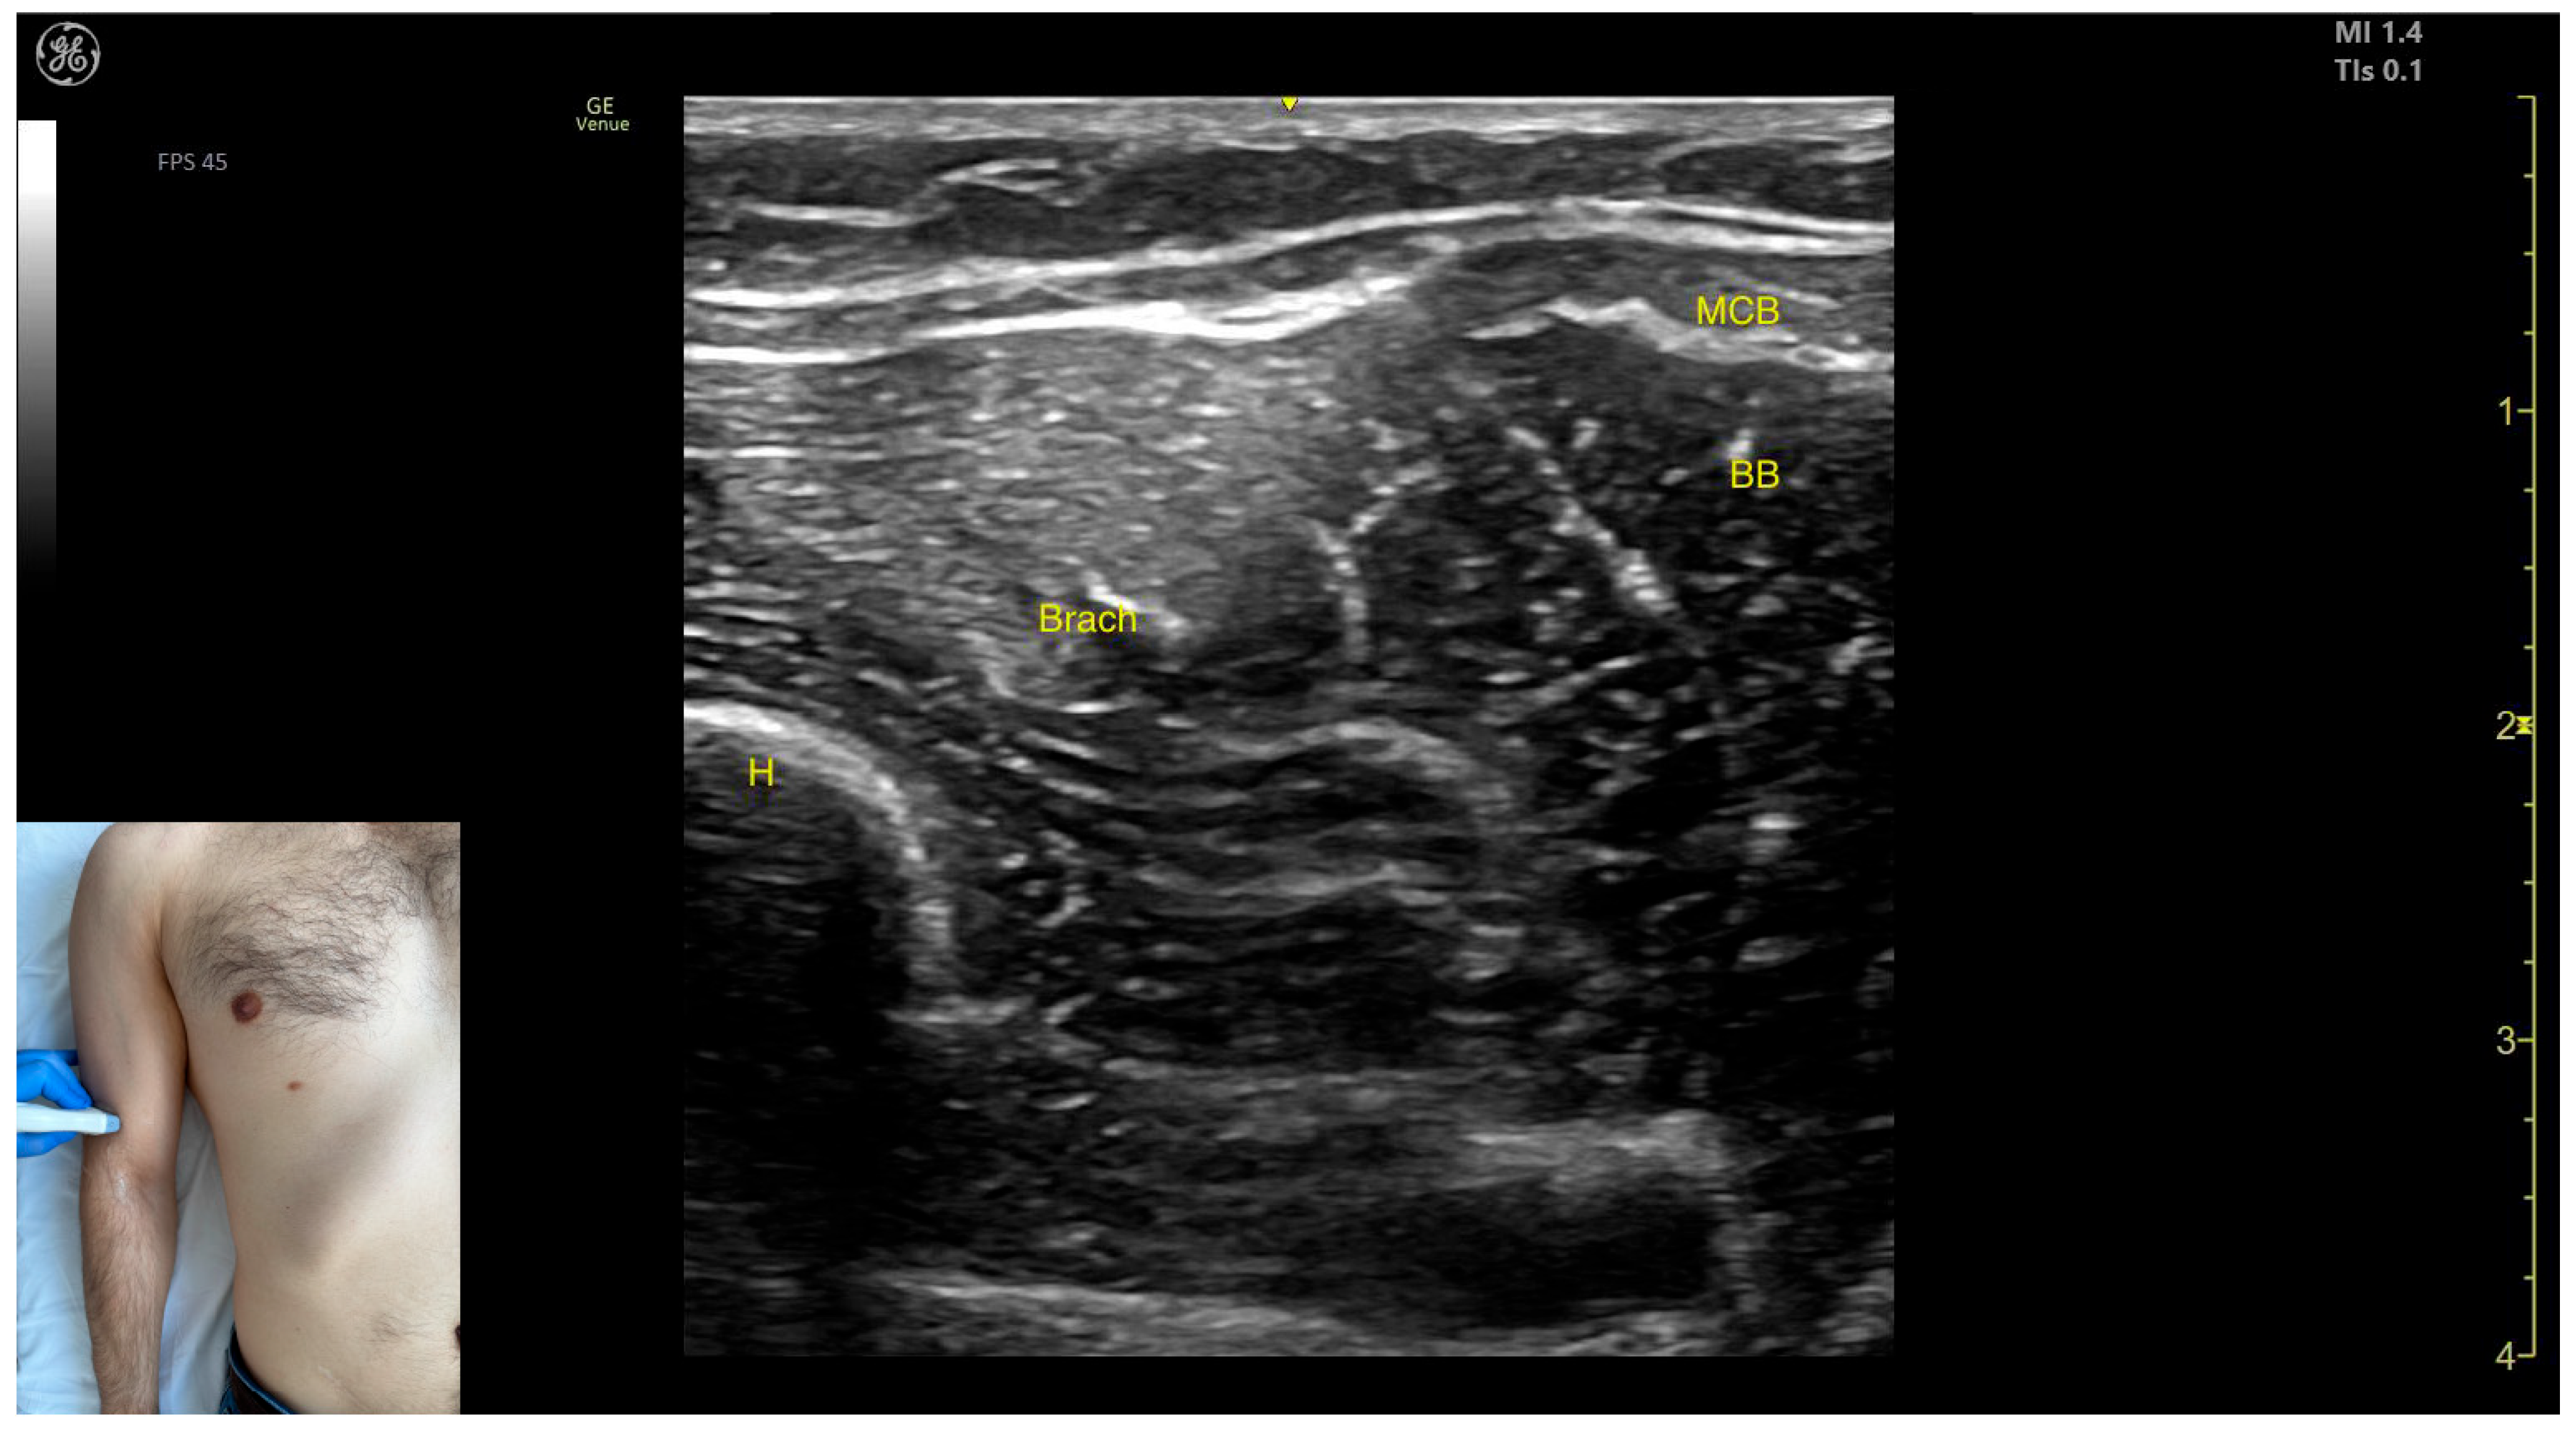

- Muscle position: It represents the most superficial muscle mass of the anterior arm at this level [57].

- Muscle morphology: It has two heads, with the long head (LHBB) located laterally and the short head (SHBB) positioned medially, separated by an intramuscular fascia that allows them to be individually targeted during procedures.

- External fascia: The BB lacks a pronounced fascia that separates it from the brachialis, which is relevant when performing BoNT-A injections.

2.9. Brachialis Muscle (Brach)

- Muscle position: It represents the first muscle mass located superficial to the cortical bone of the humerus on the anterior lateral surface of the arm.

- Innervation: The radial nerve is seen superficially in the intermuscular fascia, which separates the Brach from the brachioradialis muscle.

- External fascia: The Brach has a pronounced fascia that separates it from the brachioradialis. A very thin fascia separates it from the BB during BoNT-A injections.

- Dynamic evaluation: During dynamic evaluation, proximal scanning toward the shoulder joint shows the radial nerve moving closer to the cortical bone of the humerus before following an oblique path and disappearing from the view as it enters the posterior compartment of the arm. Medial scanning reveals the BB muscle superficial to the Brach. Muscle contraction of the Brach is visible during forearm flexion at the elbow joint, as it is the only pure flexor of the elbow [7].